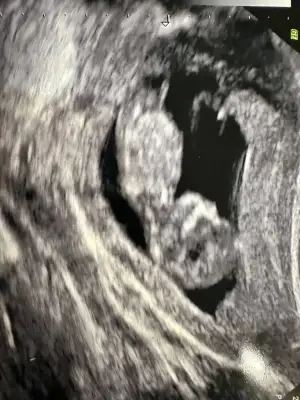

merhaba arkadaşlar rabbime şükürler olsun bende 13+2. Cinsiyet tahminleriniz beni de heyecanlandırdı. Banada yorum yaparmısınız?